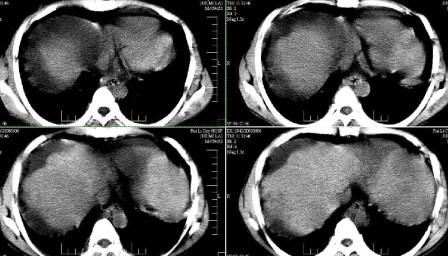

标题: CT13930:M,33岁,腹胀、腹痛10天余。 [打印本页]

标题: CT13930:M,33岁,腹胀、腹痛10天余。

右上腹压痛,肝大,质硬。腹水征。ct:肝右叶(后段)低密度影,性质待定。

1)肝癌可能;建议:行ct增强扫描检查。2)肝硬化,腹水。

肝硬化、大量腹水,肝右叶巨大肿块,境界欠清,中间见不规则低密度坏死区,考虑肝癌应该问题不大,至于肝左叶低密度灶是否转移应该意义不是很大了,慎重起见还是建议增强扫描。